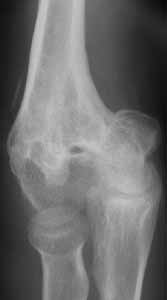

17 y/o female, had supracondylar elbow fracture in childhood which was treated by closed reduction and fixation with K-wires.

Now has elbow ROM 30-90 deg. Complaind moderate pain during activity.

I would not attempt to do anything arthroscopically here. There is much too much distortion of anatomy. I don't believe you will get her a greater arc of motion by any means. Her distal humerus is far too distorted and has developed that way. Her capitellum appears malaligned, pointing more distally than usual which is probably limiting her flexion, andthere is deformity to the ulnohumeral joint. The osteophytes are secondary, and removal may decrease some of her pain at the terminus of extension/flexion, but won't change her motion. Her arc of motion can be changed to allow her EITHER more flexionOR more extension, if an osteotomy is done, for instance- it might be moved to 60-120, or to 0-60 (not particularly functional). An osteotomy to correct the varus deformity will be cosmetic only, and one must be careful of injuring the median nerve.